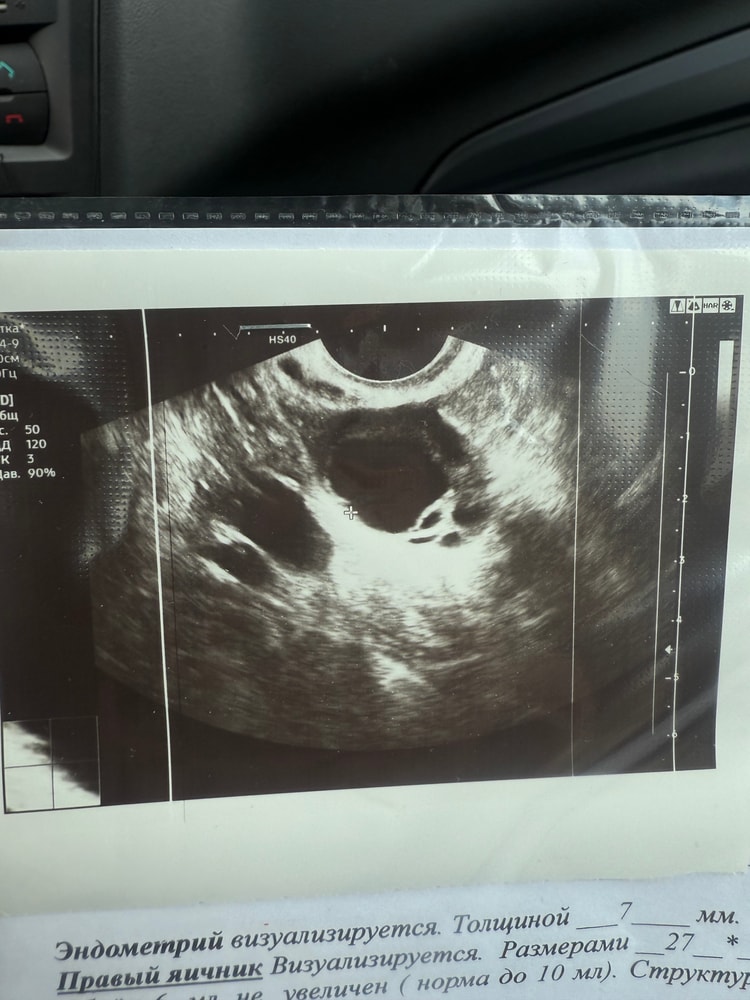

Сегодня была на узи, 14 дц. Эндометрий 7 мм, в левом яичнике есть дф 20*15 мм неправильной формы. Что это значит и чем чревато? Я так понимаю, что в этом цикле надежд уже нет, так как, скорее всего, яйцеклетка некачественная или фолик пустой (это со слов врача).